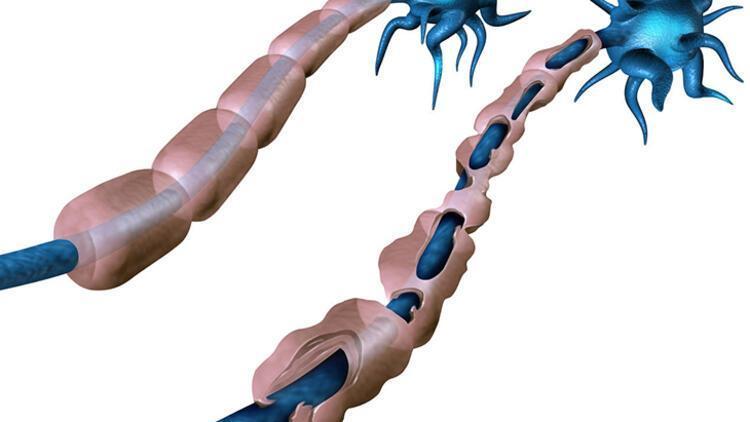

"Skleroz" denmesinin nedeni ise hastalığın beyin ve omuriliğin hasarlı alanlarında sklerozan plaklar yani sertleşmiş dokular oluşturmasıdır. Özetle MS, merkezi sinir sistemini oluşturan beyin ve omurilik üzerinde yıkıcı etkileri olan, kişinin yaşamsal fonksiyonlarını bozan ve ataklarla seyreden bir hastalıktır.

MS, vücudun bağışıklık sistemindeki normal işleyişi bozar. Bilindiği gibi normal şartlarda bağışıklık sistemi bizi hastalıklara karşı korur. Değişik nedenlerle bazen bu sistem vücuttaki normal dokuları da yabancı görmeye başlar ve onlara hücum eder.

Hastalık sinir sisteminin farklı bölgelerini farklı zamanlarda etkileyebilir. İlerleyen hastalık kişinin görme, yürüme, konuşma gibi yaşamsal öneme sahip fonksiyonlarını bozar.